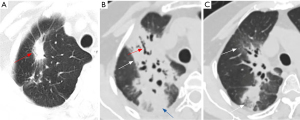

The overall incidence of grade ≥2 RP was 10.6% (5 out of 47 patients). Specifically, 5 patients (10.6%) developed grade 2 RP, with no cases of grade 3 or higher RP observed. Regarding the timing of RP development, two patients developed RP within 1 to 3 months post-radiotherapy, while the remaining three patients developed RP more than 3 months after the completion of radiotherapy. Chest CT imaging revealed RP characterized by patchy, homogeneous, and flocculent opacities localized within the irradiation field. These opacities were accompanied by thickening of vascular and bronchial structures and exhibited indistinct margins adjacent to normal lung parenchyma. The involved regions appeared denser than ground-glass opacities and demonstrated solid features with clear demarcation from surrounding normal tissues (10) (Figure 2).